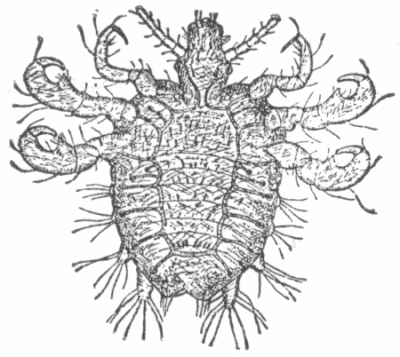

Fig. 8.

Demodex Folliculorum, X 300. Ventral surface. (After Simon).

To what may comedo often be ascribed?

To disorders of digestion, constipation, chlorosis, menstrual disturbance, lack of tone in the muscular fibres of the skin, the infrequent use of soap, and working in a dirty or dusty atmosphere. [Pg 40] A small parasite (demodex folliculorum, acarus folliculorum) is sometimes found in the sebaceous mass, but its presence is without etiological significance, as it is also found in healthy follicles. A microbacillus has been found by several observers, and credited with etiological influence.